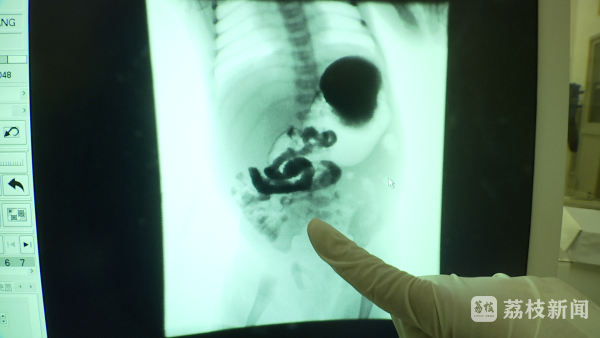

南京市儿童医院新生儿外科主任唐维兵说:“当时孩子大出血,粪便里面全部是血,血色素也很低,感染也很重,因为肠子已经烂了,整个状态都不好。”孩子一抵达医院,医生们便开始安排抢救,“做了一系列检查、紧急手术,把扭转的肠管做了复位。完全坏死的肠管做了切除,可疑的肠管我们尽量保留,如果切除过多了,那就变成短肠综合症了,这个孩子生活质量就更低了。”

“现在是术后第16天,在这16天当中他经过了好多关。”南京市儿童医院新生儿外科护士长周静一想起初见到孩子时他只有2.4公斤,就有些心疼。“一开始的时候不能经过胃肠道正常地消化吸收,必须要通过静脉营养进行吸收,各种营养剂要通过静脉打进去。”护士长介绍,这种营养液对血管的刺激性比较大,外周血管每打一次都会刺激“雨唐”一次,外周的血管也会受到破坏。“后来我们经过同意给他打了PICC,所谓的PICC就是从外周经过一定的通路到达上腔,到达血管特别粗的地方,保证他营养的供给。”

唐维兵介绍:“现在孩子的肠道功能在慢慢恢复,但是孩子毕竟处于造瘘的状态。”医生所说的造瘘状态,就指一段肠管被切断以后,从腹壁上打个洞,从肚皮上来排便。“总归还要把肠道放到肚子里去,两个断头要接起来恢复连续性,这个要过几个月,我们根据孩子的状况,选择一个比较恰当的时机把它接起来。”